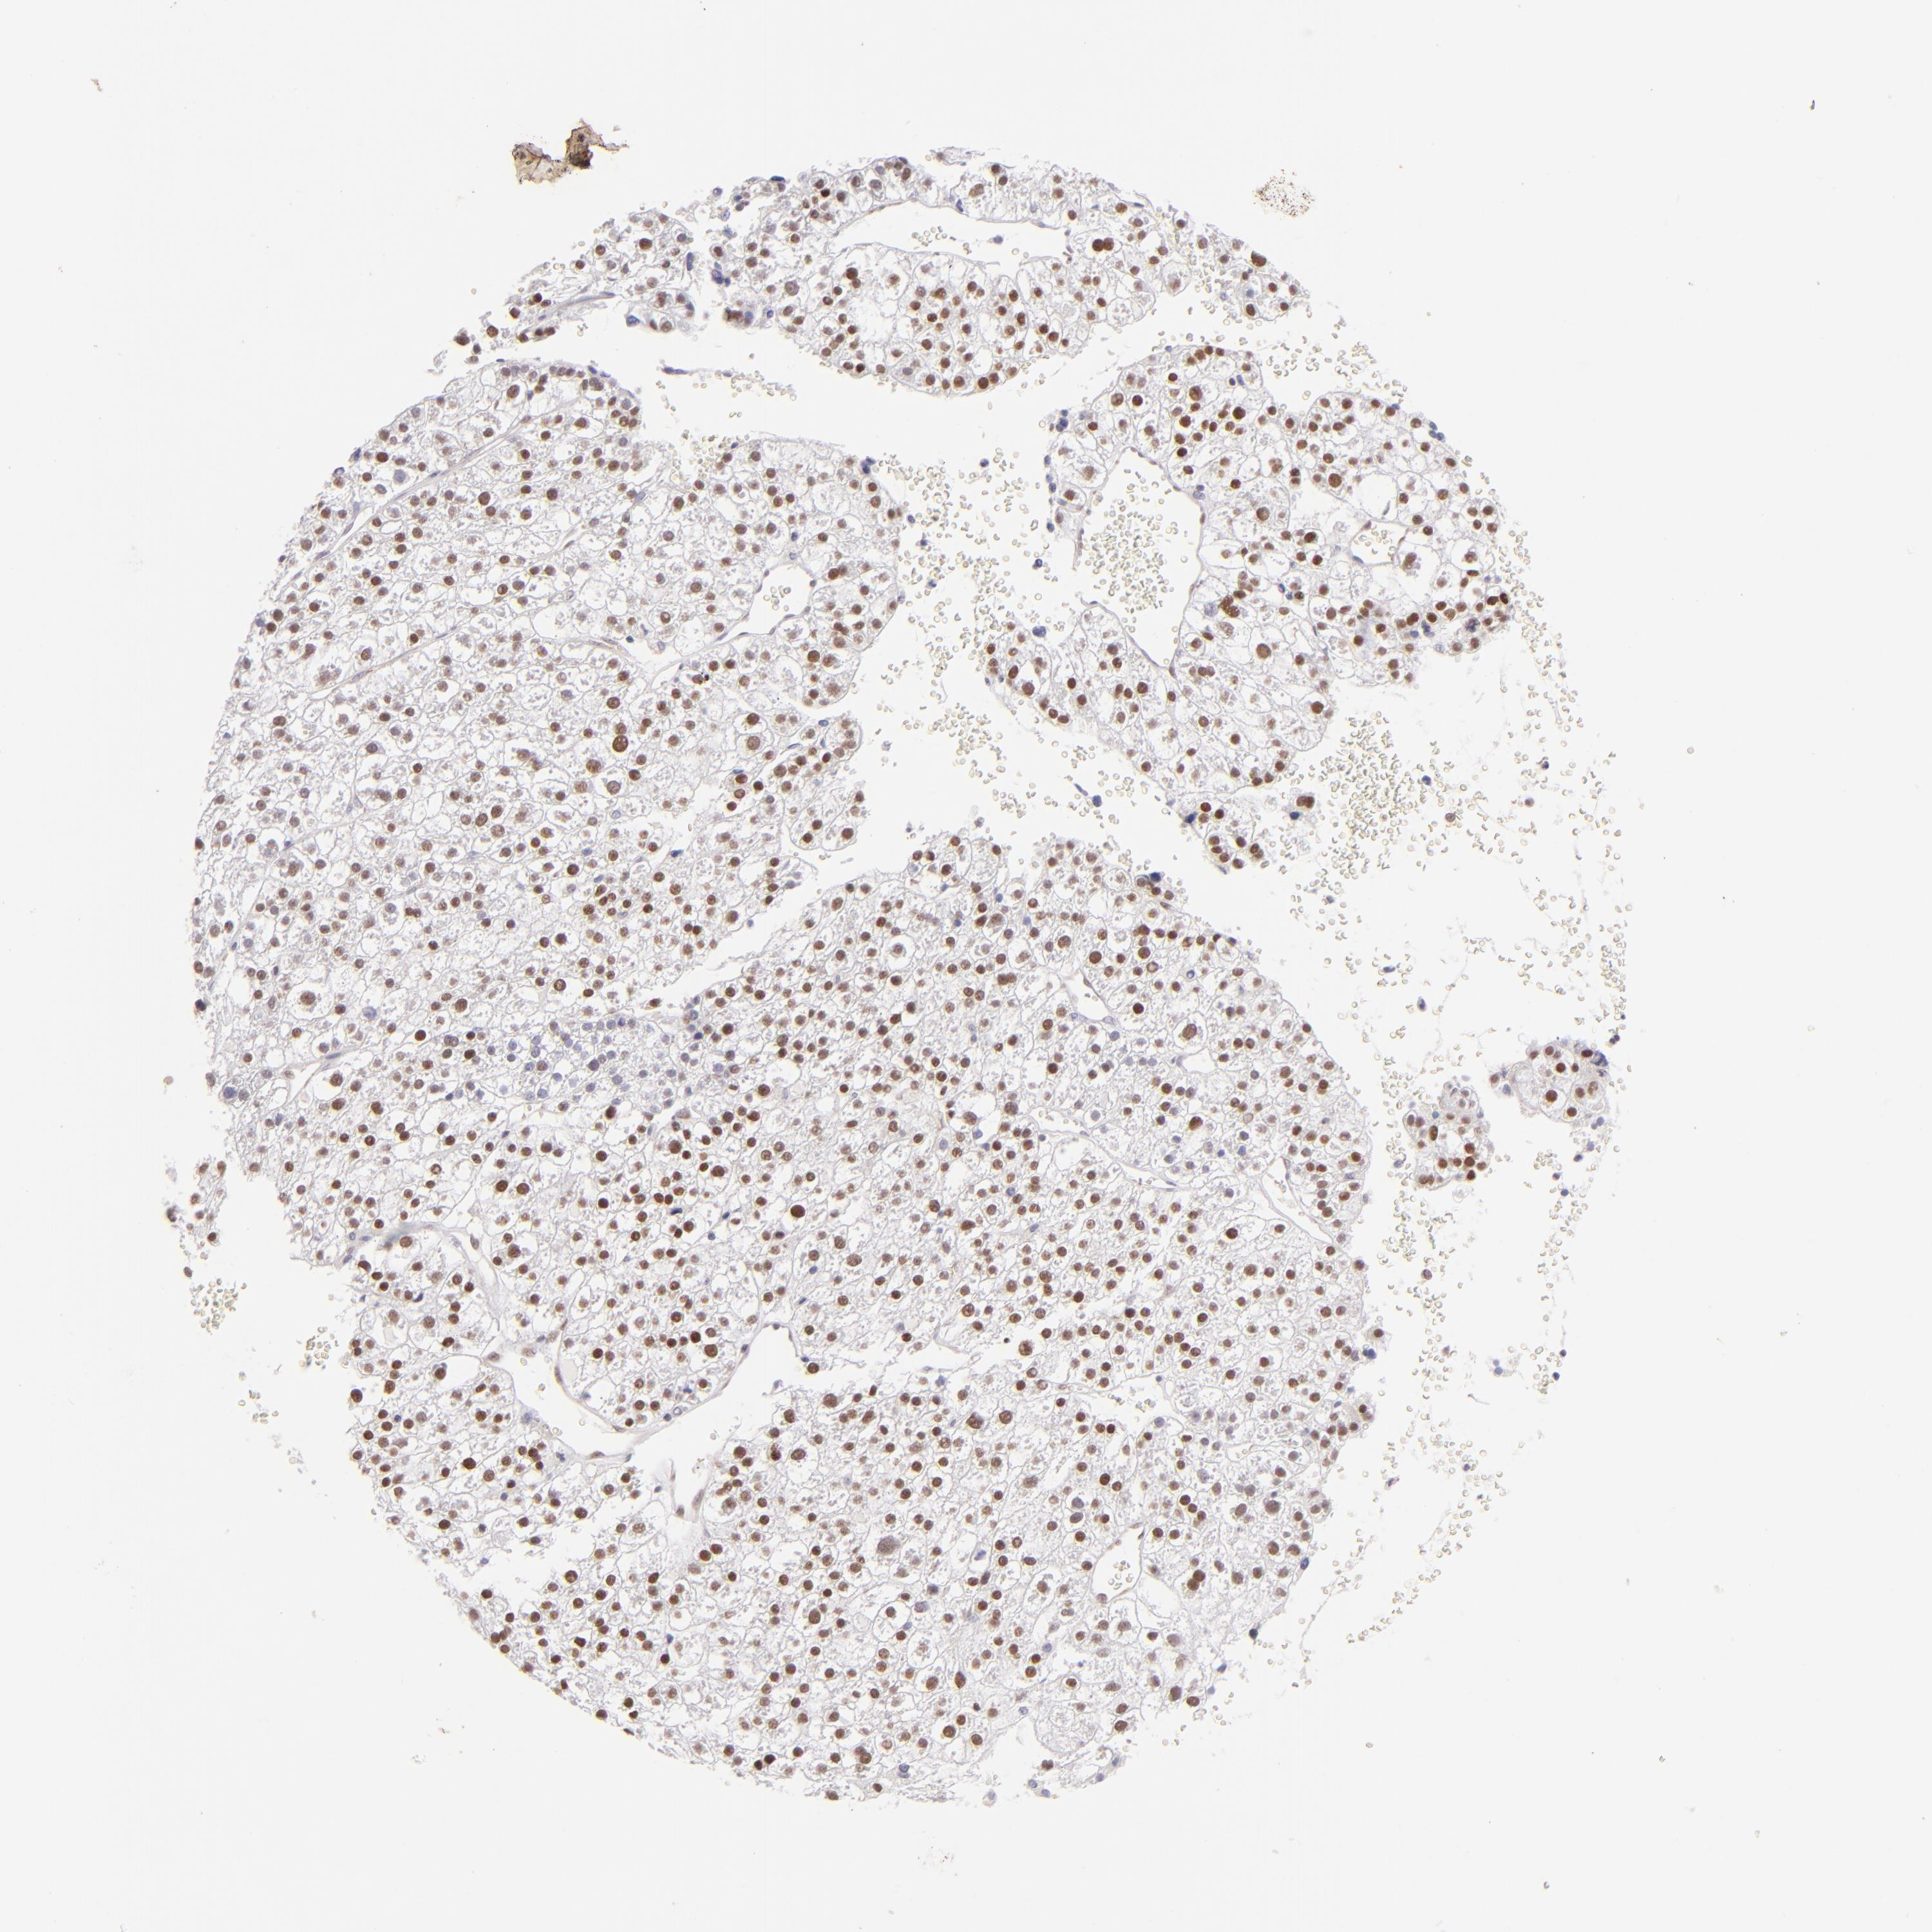

LIVER CANCER - Protein expressioni

A mouse-over function shows sample information and annotation data. Click on an image to view it in a full screen mode. Samples can be filtered based on level of antibody staining by selecting one or several of the following categories: high, medium, low and not detected. The assay and annotation is described here.

Note that samples used for immunohistochemistry by the Human Protein Atlas do not correspond to samples in the TCGA dataset.

Antibody stainingi

Antibody staining in the annotated cell types in the current human tissue is reported as not detected, low, medium, or high, based on conventional immunohistochemistry profiling in selected tissues. This score is based on the combination of the staining intensity and fraction of stained cells.

Each image is clickable and will lead to virtual microscopy that enables deeper exploration of all samples and also displays staining intensity scores, fraction scores and subcellular localization as well as patient and tissue information for each sample.

Antibody HPA064323

Antibody CAB002608

Staining

High

Medium

Low

Not detected

Intensity

Strong

Moderate

Weak

Negative

Quantity

>75%

75%-25%

<25%

None

Location

Nuclear

Cytoplasmic/membranous

Cytoplasmic/membranous,nuclear

Carcinoma, Hepatocellular, NOS

Cholangiocarcinoma